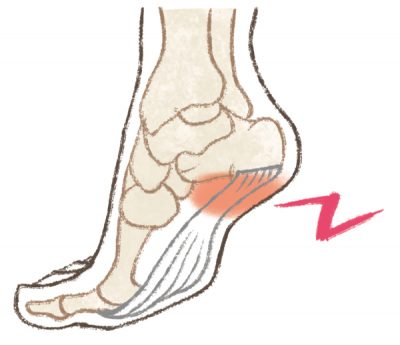

シーバー病【踵骨骨端症(しょうこつこったんしょう)】は、10歳前後の男児に多くみられる病気で、かかとの軽い腫れ、押すと痛みが出る、歩行時痛がその主な症状です。

シーバー病【踵骨骨端症(しょうこつこったんしょう)】は、10歳前後の男児に多くみられる病気で、かかとの軽い腫れ、押すと痛みが出る、歩行時痛がその主な症状です。

過度な運動のあとに症状が出ることが多く、かかとの痛みのために、つま先歩きになることもあります。

かかとの骨である踵骨は、成長の過程で一つのしっかりとした骨になっていくのですが、成長期までは「踵骨骨端核(しょうこつこったんかく)」と「成長軟骨」に分かれており、非常に脆い状態です。

成長期の子どもの弱い踵骨骨端部(かかとの骨の端でアキレス腱が付着しているところ)に運動などで負荷がかかり、そこにアキレス腱の引っぱる力が持続的に加わることで、踵骨に血流障害が起こり、かかとの軟骨部の壊死、または骨軟骨炎を発症するのがこの病気です。